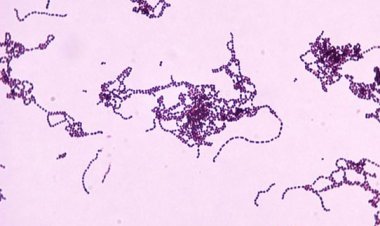

Esta es una bacteria que puede generar cuadros infecciosos graves hasta un proceso...